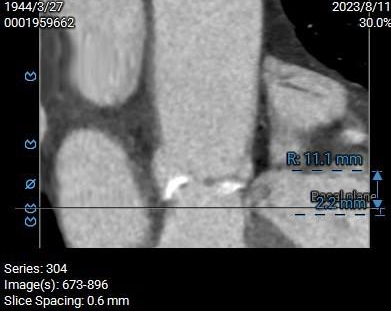

膜部室间隔2.2mm,主瓣二尖瓣夹角可:

左心耳及心室未见血栓,瓣环水平夹角57°,近横位心: